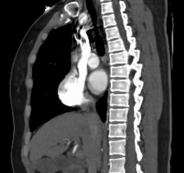

△注:患者出院后定期我科门诊复查,术后2月复查提示支架完美重建胸主动脉血管通路,原夹层内部基本血栓化,未发现相关并发症。